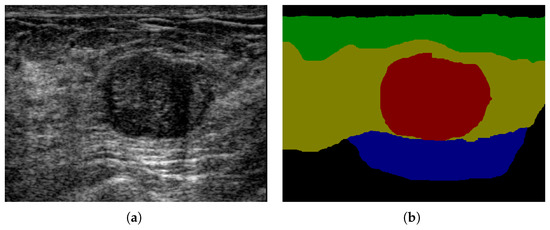

4.4. Multi-Object Semantic Segmentation of BUS Images

4.4.4. Semantic Segmentation Results

| Multi-layer Dataset | 325 | Fat/Mammary/Muscle/Tumor/Background |